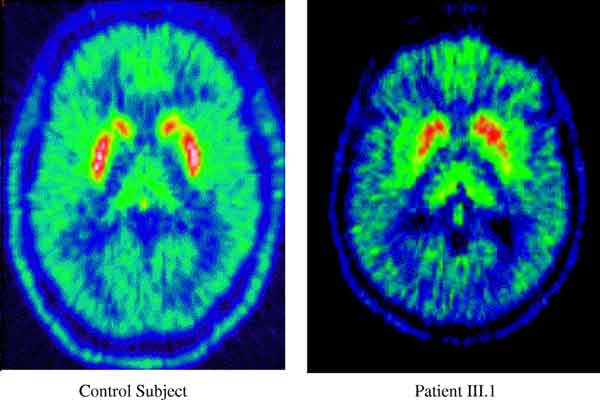

Quelli che hanno vissuto in aree in cui era usato l’erbicida Paraquat e che hanno subito infortuni alla testa hanno una probabilita’ tre volte maggiore di ammalarsi di Parkinson. Lo studio della University of California di Los Angeles e’ pubblicato sulla rivista ‘Neurology’. Il Paraquat e’ un erbicida comunemente usato sul frumento per tenere sotto controllo le erbe infestanti: puo’ essere mortale per animali e umani. “Entrambi questi fattori, presi singolarmente, aumentano il rischio Parkinson. La combinazione fa crescere ancora di piu’ questa probabilita’”, ha spiegato Beate Ritz, fra gli autori della ricerca.

“Probabilmente, dunque, i processi fisiologici innescati da un trauma alla testa aumentano la vulnerabilita’ delle cellule cerebrali all’attacco dei pesticidi, e un’esposizione cronica a basse dosi di queste sostanze puo’ aumentare il rischio del Parkinson”. Lo studio ha coinvolto 357 malati di Parkison e 754 persone senza la malattia che vivevano in aree agricole nella California centrale. Ogni partecipante riportava li traumi cerebrali che aveva subito e che avevano comportato una perdita di coscienza di almeno 5 minuti. Le persone con il Parkinson avevano il doppio di probabilita’ di aver subito un colpo alla testa con perdita di coscienza superiore ai cinque minuti rispetto a quelle che non avevano subito questo infortunio. Le persone con Parkinson avevano il 36 per cento in piu’ di probabilita’ di essere stati esposti al paraquat rispetto a quelli che non avevano la malattia. Fra i malati di il Parkinson, in 169 erano stati esposti al diserbante (47 per cento), rispetto ai 291 dei soggetti senza la malattia (39) .